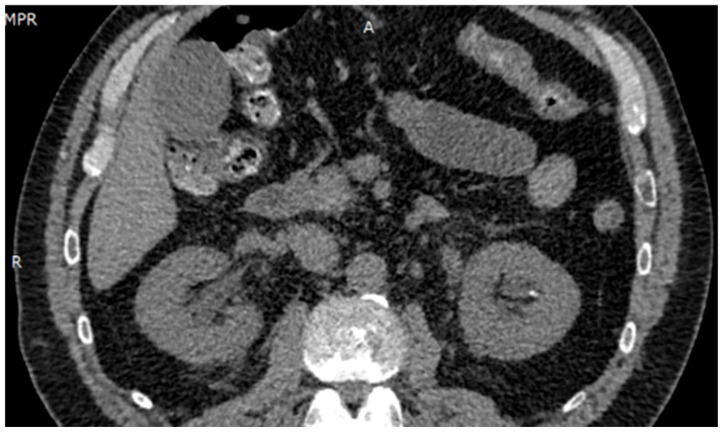

Background/Objectives: Acetazolamide is widely used for acute mountain sickness (AMS) prophylaxis. Whilst generally safe, acute kidney injury (AKI) is a rare but serious adverse event. We present a case of anuric AKI following minimal exposure to acetazolamide, contributing to the limited literature on its nephrotoxicity at prophylactic doses. Methods: A 54-year-old previously healthy male ingested 250 mg/day of oral acetazolamide for two days. He developed acute anuria and lumbar pain. Diagnostic evaluation included laboratory tests, imaging, microbiological cultures, autoimmune panels, and diuretic response. No signs of infection, urinary tract obstruction, or systemic disease were found. Results: The patient met KDIGO 2012 criteria for stage 3 AKI, with peak serum creatinine of 10.6 mg/dL and metabolic acidosis. Imaging confirmed non-obstructive nephrolithiasis. Conservative treatment failed; intermittent hemodialysis was initiated. Renal function recovered rapidly, with the normalization of serum creatinine and urinary output by day 4. Conclusions: This case represents the lowest cumulative dose of acetazolamide reported to cause stage 3 AKI. The findings support a pathophysiological mechanism involving sulfonamide-induced crystalluria and intratubular obstruction. Physicians should consider acetazolamide in the differential diagnosis of AKI, even with short-term prophylactic use.